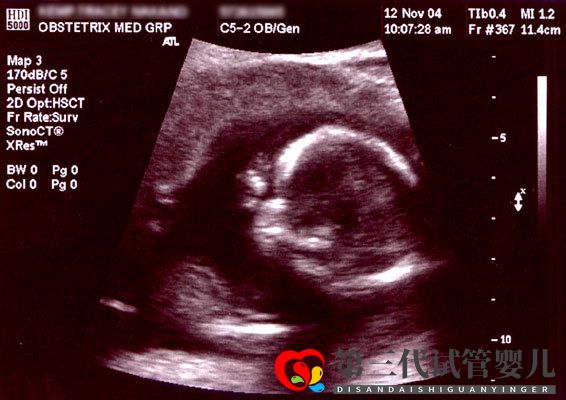

第三代試管嬰兒技術是目前成功率最高的試管嬰兒技術,經過人工培育以及養囊之后,胚胎就要經過PGS/PGD技術篩選。目前此項技術能檢測出274種基因遺傳疾病以及檢測胚胎染色體結構與數量是否正常,再通過人工挑選出最優質、最健康的胚胎移植。這樣做不但能保證胎兒的健康,還能大幅增加移植的成功幾率。